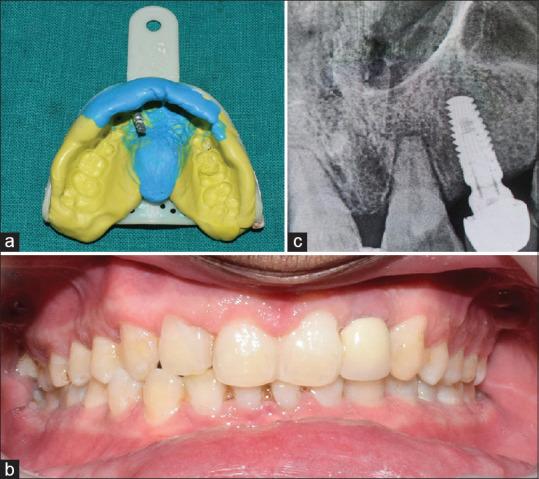

To assess the effect of advanced platelet-rich fibrin (APRF) and concentrated growth factor (CGF) on tissues around implants in the maxillary anterior region.

Thirty subjects were divided into three groups with 10 dental implants in each group, i.e., Group 1: Control group, Group 2: Endosseous implant placement with APRF, and Group 3: Endosseous implant placement with CGF. The subjects were assessed at baseline (at the time of prosthesis placement), 2 weeks, 2 months, 6 months, and 1 year for modified sulcular bleeding index, periimplant probing depth, mucosal suppuration, bleeding on probing, crestal bone level as well as implant stability.

The difference in implant stability at 2 months was significantly (P < 0.05) more among the control and CGF groups compared to APRF group. However; the crestal bone levels, periimplant probing depth, modified sulcular bleeding index, mucosal suppuration, and bleeding on probing were statistically non-significant (P > 0.05).

CGF and APRF accelerated osseointegration. Furthermore, they had a positive effect on stabilization values. However, CGF showed better results and with further clinical trials may show a positive effect on implant healing period.